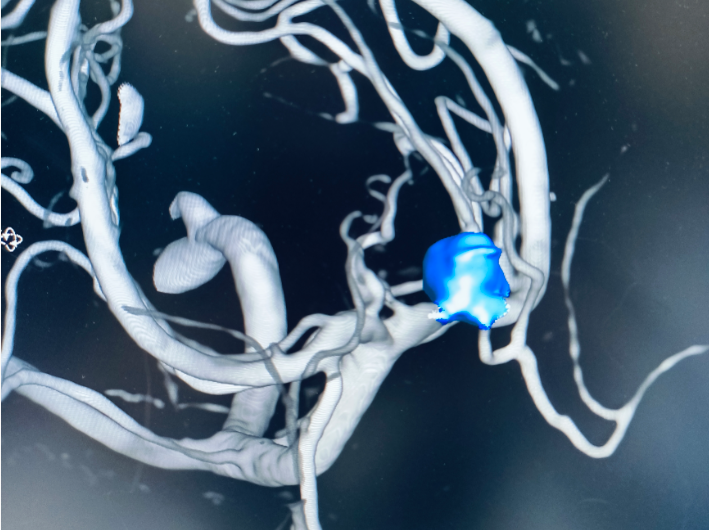

由于病情危急,当地医院初步检查后建议转至上级医院进一步治疗。随后,小张被 120 急救车转运至昆明三博脑科医院。医院紧急开通绿色通道,神经外科医护团队第一时间介入,结合头颅影像学检查结果,小张被确诊为 「颅内动脉瘤破裂出血」。

颅内动脉瘤被称为大脑里的 「不定时炸弹」,一旦破裂出血,血液会压迫脑组织,若不及时干预,不仅可能造成严重的语言障碍、肢体偏瘫,甚至会危及生命。情况刻不容缓,神经外科专家团队迅速制定手术方案,为小张紧急实施了 「脑动脉瘤介入栓塞术」。经过医护人员的全力救治,小张的出血情况得到控制,术后恢复良好,目前已脱离险境,即将康复出院。